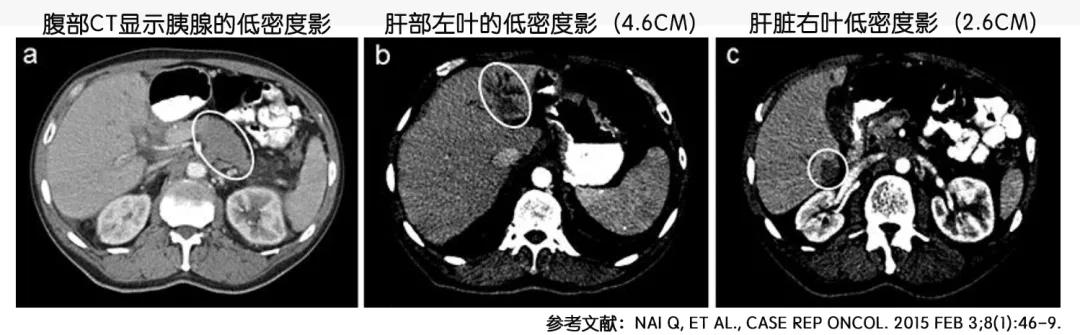

图2 腹部CT显示胰腺癌以及可能的肝脏转移

2013年,这个患者因为反复出现腹痛和持续性体重降低而入院。这一次CT影像学检查显示胰腺远端和胰腺尾部有恶性肿瘤。而且肝部、脾、左肾和门静脉有血栓。经过对肝部病灶进行的穿刺活检证实为原发性胰腺腺癌。